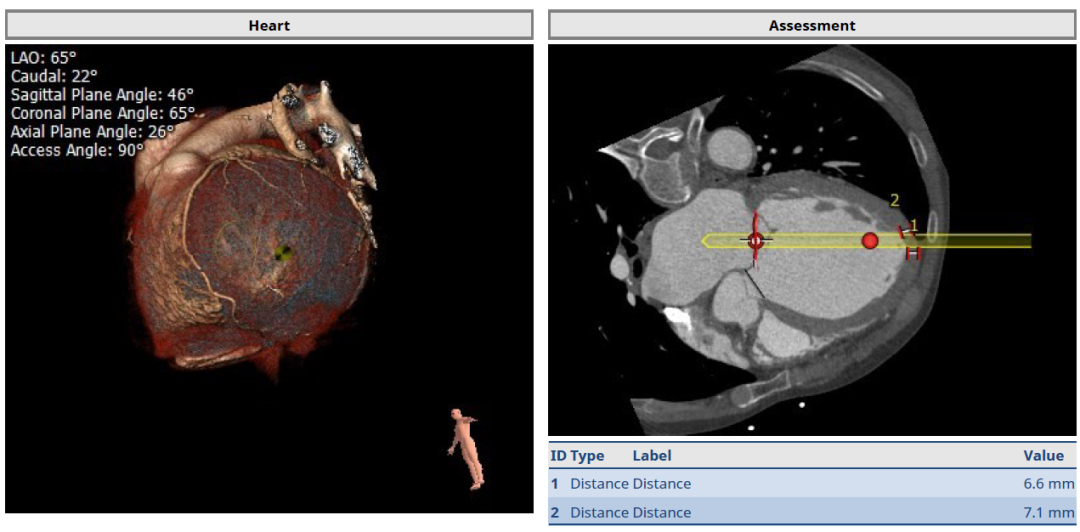

经过瑞金医院心外科MDT团队综合讨论评估该患者病情后,患者为重度FMR患者,为传统外科手术极高危患者,决定进行MitraFix®经心尖二尖瓣植入。术前心脏CTA瓣环面积折算最大直径41.5 mm 模拟植入34号二尖瓣瓣膜, 心室Neo LVOT面积可。

术前瓣环形态评估

术前心尖入路评估